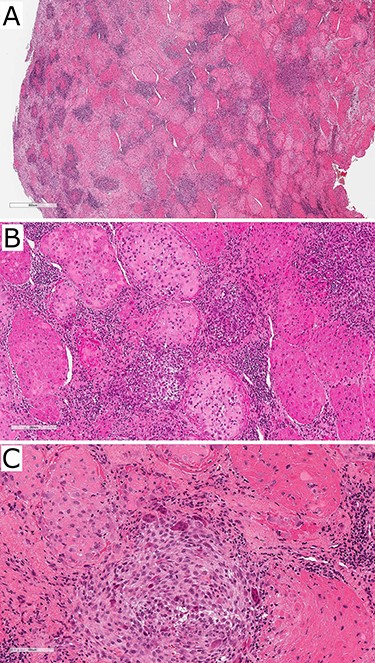

The patient was regularly reviewed reporting no improvement to stiffness on mouth opening. At her 3-month post-operative review, she complained of worsening stiffness to mouth opening. A follow-up CT of the TMJs portrayed extensive progressive bony erosion to the mandibular condylar head. This provoked a discussion with the pathologist to reconsider the diagnosis of the previously sent specimen. A histopathological revision reported a chondroid fibrohistioctyic lesion with overall features more in keeping with PVNS with chondroid metaplasia (Fig. 3).

Photographs of haematoxylin and eosin-stained slides of the resected tissue sample showing fibrohistioctyic areas in addition to cartilaginous nodules. Magnification (A) ×94, (B) ×375, (C) ×750.

Chondroid TGCT can mimic other cartilage-forming pathologies such as chondrosarcoma and synovial chondromatosis rendering its diagnostic challenge even greater [3, 6]. Between CT and MRI, chondroid TGCT manifests as an erosive bony lesion with its extent reliably identified. Focal hypointense areas on MRI are characteristic features secondary to the blooming artefact caused by the haemosiderin in the lesion [7, 8]. Definitive diagnosis is made histopathologically typically identifying fibrohistioctyic lesions comprised of plump histiocytoid cells and multinucleated giant cells, cartilaginous nodules and haemosiderin deposition [6]. Varying degrees of chondroid metaplasia is seen in the chondroid subtype [3]. Due to the aggressive locally destructive nature of the disease, D-TGCT treatment necessitates surgical resection of all affected tissue with clear margins. Reconstructions vary from bone grafts, total joint replacement to free vascular graft. Adjuvant radiotherapy may be utilized with extensive disease in difficult attainable sites or residual disease [8]. Recurrence of D-TGCT of the TMJ (9%) is lower than in other joints (8–46%); however, the accuracy of this comparison remains unclear given the rarity of this disease involving the TMJ and lack of longitudinal data [4].